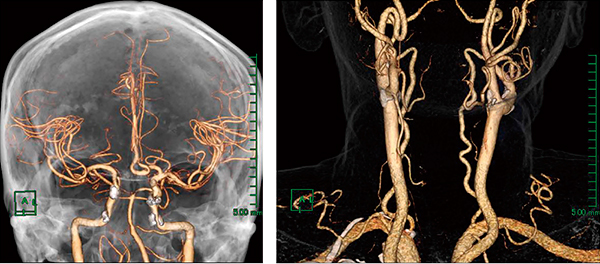

頭部・頸部血管(時間短縮)

VirtualPlaceのサブトラクションは動脈系の血管末端の抽出に優れている利点があり,Aquilion ONEのサブトラクションは椎骨動脈・総頸動脈などの骨に隣接している血管の抽出に優れている利点がある。この互いの利点を利用して,それぞれのサブトラクション画像をVirtualPlaceに取り込みマルチボリュームフュージョンを活用することで,3D構築画像やMIP画像をより早く診療医に提供できる(図6)。

図6 頭頸部の血管の描出

石灰化抽出は必要だが,従来と比べてかなりの時間短縮につながる。